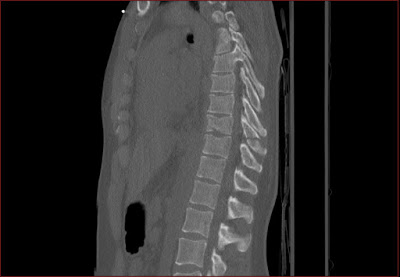

Csigolyatores a thoracalis gerincszakaszon Szerző: admin | jún 10, 2010 | Fracture, Pneumothorax, Trauma | Nincsenek hozzászólások A csigolyatest felso zarolemezt is erinto elulso torese tores a processus spinosuson